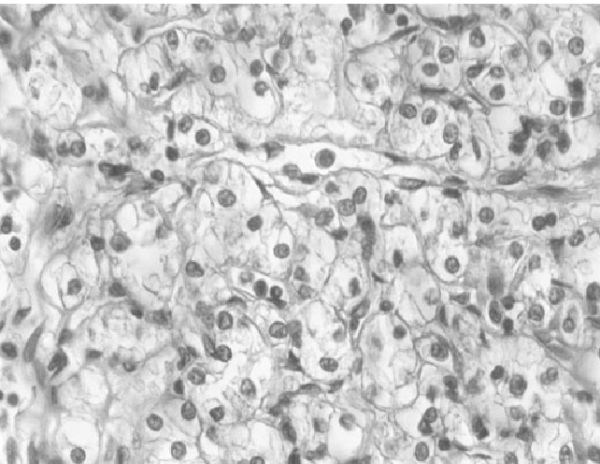

Sistema de graduación nuclear de Fuhrman

El grado nuclear de Fuhrman es un sistema de clasificación utilizado principalmente para evaluar las características de los núcleos de las células tumorales en los casos de carcinoma de células…

Carcinoma de células renales

El carcinoma de células renales (CCR) y el carcinoma de la pelvis renal representan aproximadamente el 3,8% de todos los cánceres en adultos, lo que subraya su relevancia en la…